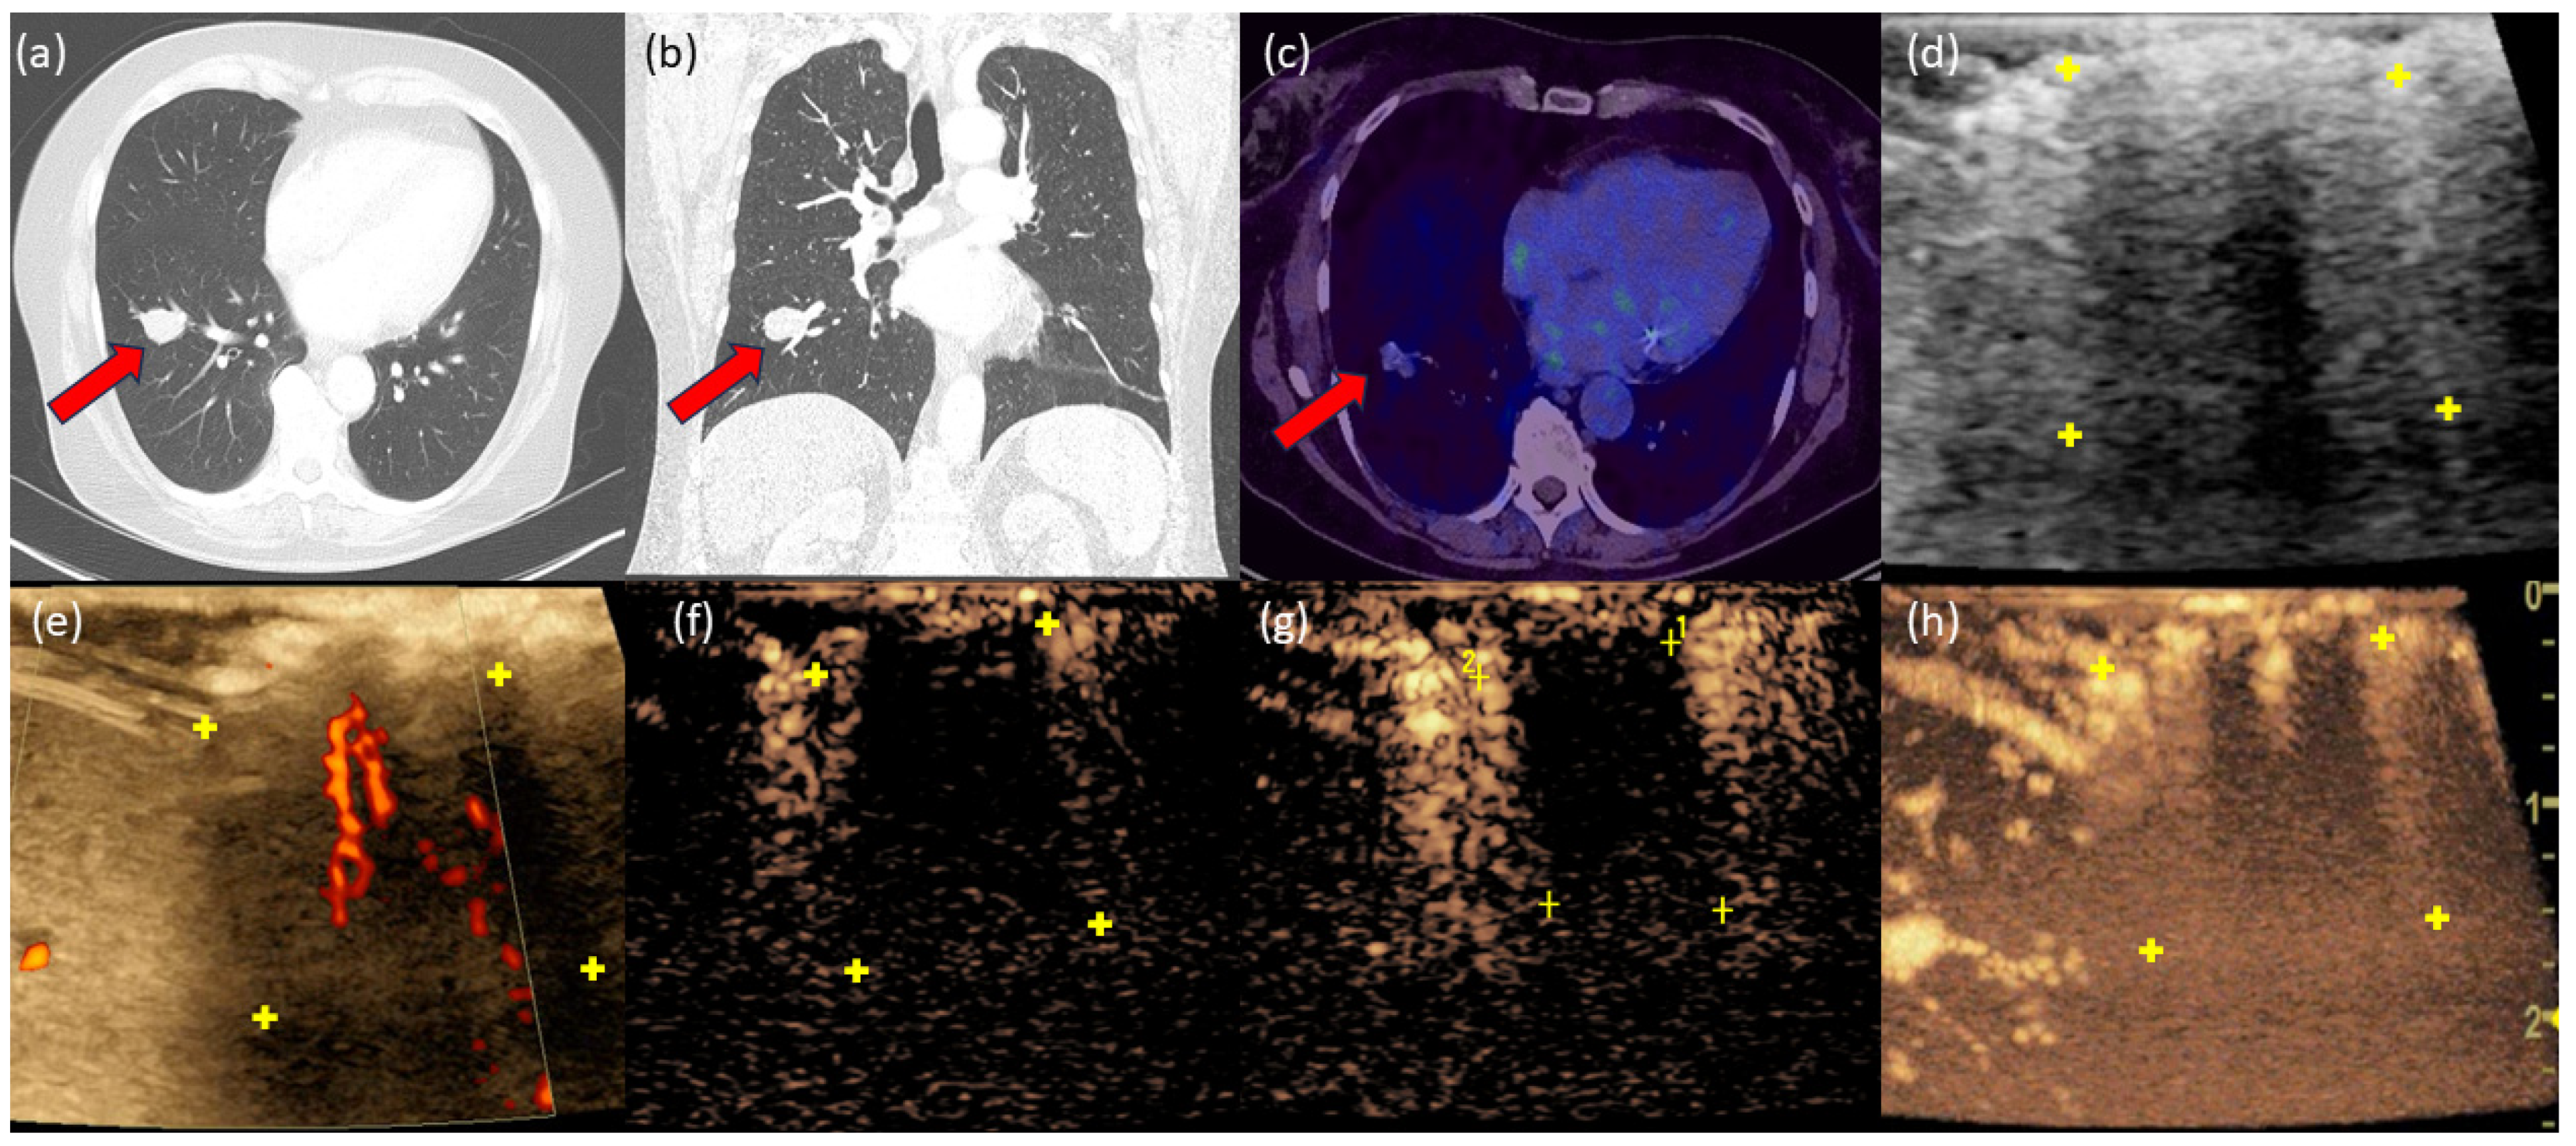

3.6. Case 2